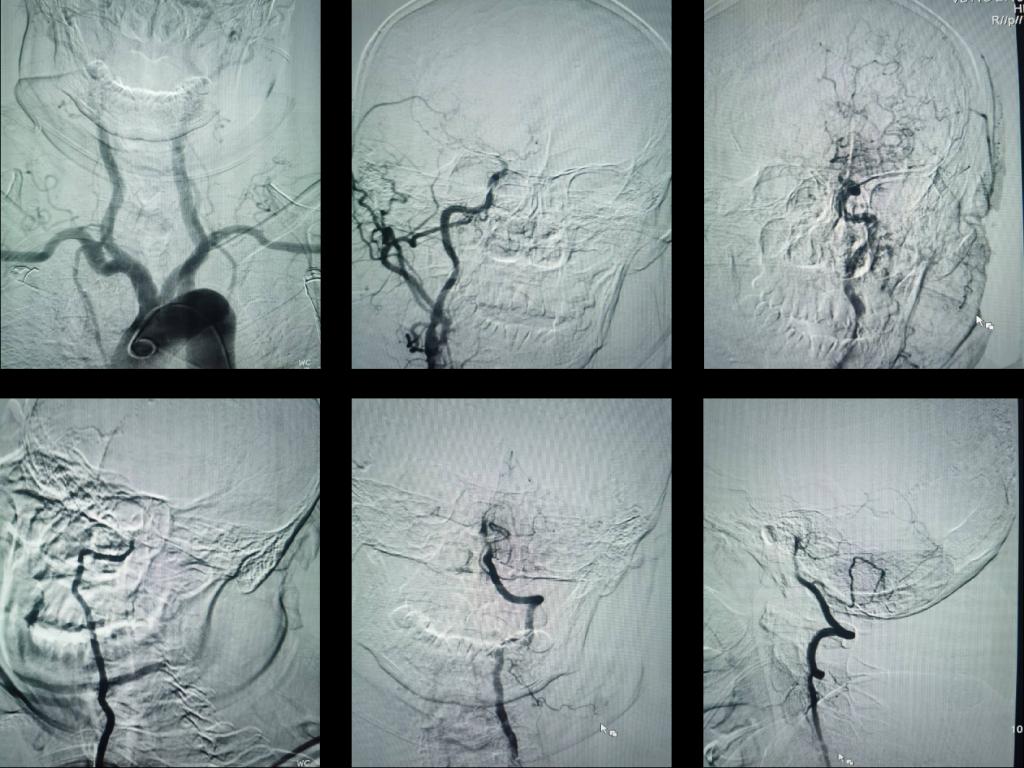

患者已处于重度昏迷。神经内科介入小组(高震主治医师、瞿慧阳医师、张倩护士和蒋鹏鹏护士)和当天值班二线李燕玲主治医师第一时间赶到现场,协同完成术前准备并推入导管室。消毒-铺巾-穿刺-超选-打药,脑血管造影显示患者大脑前部血管均为烟雾血管,没有主干,唯一赖以生存的椎基底动脉完全堵塞。

图2 颈动脉末端闭塞,血管呈烟雾样表现,椎基底动脉堵塞

患者命悬一线,刚刚结束一天工作的王虎清教授,用最短时间评估并制定了手术方案。家属态度积极,签字同意手术。高震主治医师和瞿慧阳医师采用经典的抽拉结合动脉取栓(SWIM术式)和球囊扩张技术在20分钟内实现了闭塞的基底动脉完美再通。

图3 采用经典抽拉结合动脉取栓(SWIM术式)和球囊扩张技术在20分钟内实现了基底动脉闭塞完美再通